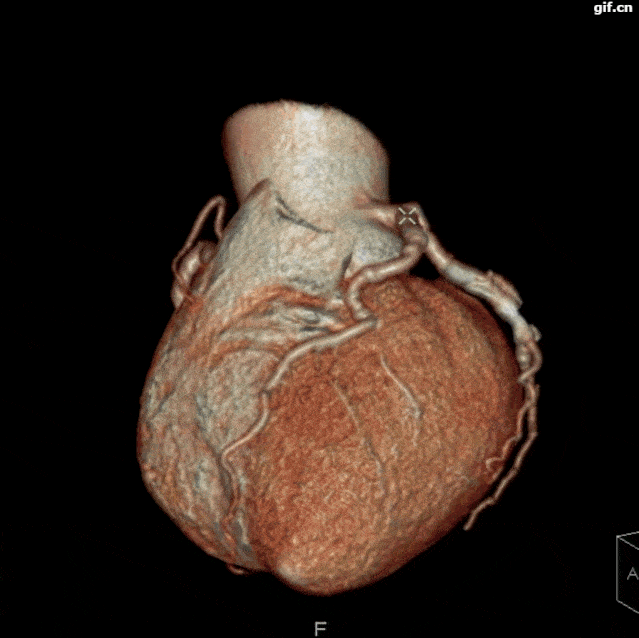

03 30ms快門極速心臟成像 揭開“心”的謎底

以最快的時間分辨率,捕捉高清小焦點冠脈成像,最大程度地克服冠脈高速搏動、冠脈運動節奏和規律紊亂、三支主要冠脈運動不一致等難題。

冠狀動脈多發斑塊